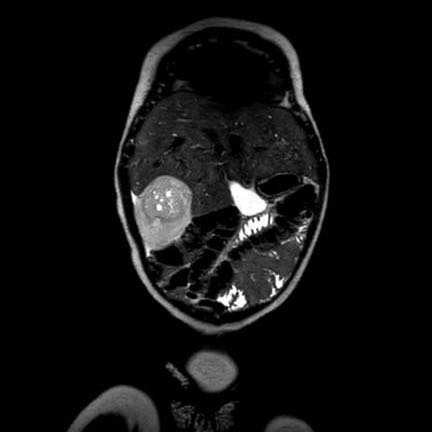

Hình ảnh

Siêu âm và MRI của bé trai bốn tuổi với tổn thương dạng nang đa thùy ở vùng cực giữa thận trái (mũi tên).

Tổn thương được phát hiện tình cờ khi bé được chín tháng tuổi. Trong quá trình theo dõi, không ghi nhận sự thay đổi nào. Tổn thương phù hợp với u thận dạng nang, một tình trạng lành tính.

Tổn thương tương tự được quan sát trên ảnh chuỗi xung T2W mặt phẳng ngang.